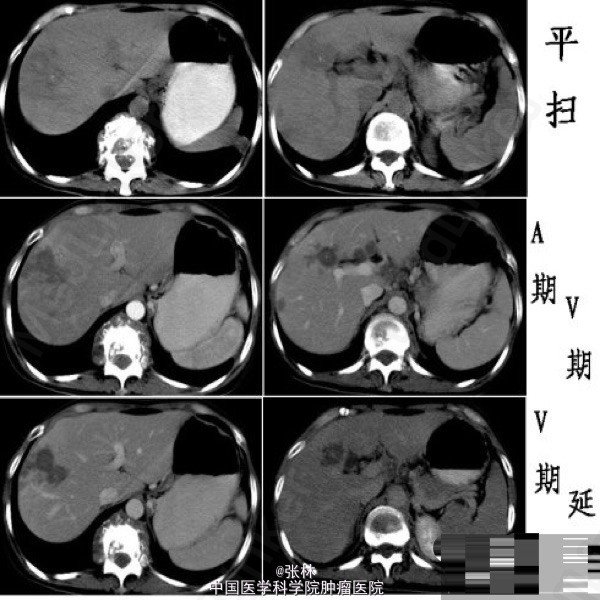

病史:女性,41岁,肝区不适伴反复双肾区疼痛1年。 上腹CT:肝内多发斑片状或类圆形灶状密度异常,占位效应不明显,边界模糊,平扫呈不均匀稍低密度,局部可见点状高密度钙化影。增强扫描:动脉期病变周围正常肝实质可见片絮状轻度一过性强化,病变内部可见强化的小血管影;静脉期病变呈低密度影,内部无明显强化;延迟扫描病变范围缩小,周边轻度强化。 影像检查发现:T10至L1椎体破坏,并冷脓肿形成;左下肺结核。 临床诊断:肝结核、脊柱结核、肺结核。 肝结核 Hepatic tuberculosis 肝结核是一种少见病,且多继发于其他器官结核的播散。 发生在肝实质的结核大致可分为:粟粒型、结节型和混合型。 (1)粟粒型:较常见,为多发或弥漫粟粒状小结节灶(直径≤2cm),常为全身结核的一部分,临床诊断并不十分困难。影像学可见肝肿大和细小结节灶。对非钙化性病灶直径< 0.5 cm者,CT、MR检查大多难以发现。 (2)结节型:直径> 2 cm,较少见,由粟粒灶或细小结节灶融合而成,因易于发现而国内外文献报道多为这一类型。若结核性肉芽肿液化坏死不明显或病灶以纤维组织为主,CT表现为低密度肿块影,病灶可呈轻度边缘强化,影像学表现无特征,诊断困难。当结核性肉芽肿内钙盐沉着时,可在病灶内出现斑点状甚至“粉末状”钙化灶,有一定的特征性。 (3)混合型:即粟粒大结节型,CT表现为多发粟粒状钙化伴单发结节状低密度灶。多发不同密度改变的病灶为肝结核较为特征的CT征象。这种表现反映肝结核同时存在不同病理时期的病灶,包括结核性肉芽肿、液化坏死、纤维化或钙化。 肝结核的其他表现:腹腔淋巴结肿大;“卫星灶”;脾肿大或感染结核;肝外结核史或结核接触史。肝外结核史在肝结核的诊断中尤为重要。